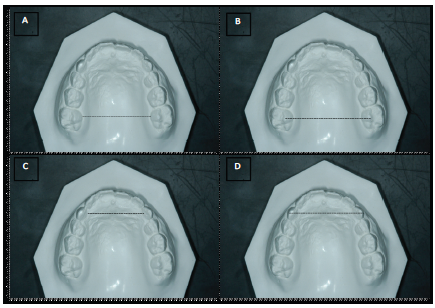

The following cephalometric measurements were evaluated: SNA, SNB, ANB, SN.GoGn, SN.PP, 1.PP and 1.PM (McNamara Jr., 1984) (Figure 2). The lateral cephalograms were scanned (HP Scanjet G4050, USA) and imported to a cephalometric analysis program (Cef X, CDT Softwares, Campo Grande, Brazil) (Figure 1). Intercanine and intermolar distances were measured on the plaster casts at T0, T1, T2 and T3 with the aid of a digital caliper (precision: 0.01 mm) (Mitutoyo-Japan). Four measures were made: A) gingival intermolar distance (union between palatal gingival margin and tooth); B) cusp intermolar distance (mesiopalatal cusps); C) gingival intercanine distance; and D) cusp intercanine distance (Lagravere, Major, Flores-Mir, & Orth, 2005) (Figure 3). The difference between the cusp and gingival measures allowed the determination of whether RME caused inclination of the teeth. One month after first measures, 50% of the lateral cephalograms and dental casts were randomly selected and the measures were repeated.

No statistically significant differences were found in the intercanine distances or intermolar distances between T0 and T1, indicating that the RME does not cause inclination of the teeth. A small relapse was found in both the canine and molar regions, but this relapse did not achieve statistical significant (T2 – T1 and T3 – T2). Gains in the transverse dimension were found in both the canine and molar regions (T3 – T0), with no statistically significant difference between these regions (Table 3).

Besides the increase in the width of the upper arch (Geran et al., 2006; McNamara Jr., 1984; Podesser, Williams, Crismani, & Bantleon, 2007; Christie, Boucher, & Chung, 2010; Weissheimer et al., 2011) studies have reported a greater transverse increase in the anterior region in comparison to the posterior region (Lagravere et al., 2005; Bayram et al., 2001; Christie et al., 2010). In the present investigation, however, similar increases were found in both regions (Table 3), demonstrating parallel expansion. This finding is in agreement with data reported in previous studies (Rungcharassaeng et al., 2007; Podesser et al., 2007; Christie et al., 2010). In a systematic review carried out by Lione, Franch, & Cozza (2013) the authors concluded that the intense forces applied for short periods in growing patients move the anchoring teeth and alveolar bone at the same magnitude and in the same direction. Analyzing possible differences between appliances that concentrate the expansion in the anterior region (fan-type rapid maxillary expansion) and those that concentrate the expansion in the posterior region (RME), Çörekçi & Göyenç (2013) found that the transverse increase in the intercanine region was similar with both appliances, but the transverse increase in the intermolar region was significantly greater in the RME group.

RME is the treatment of choice in cases of maxillary transverse deficiency due to its speed and predictability as well as the little orthodontic effect on the inclination of the teeth. Although the present study did not evaluate the expansion of the buccal bone related to inclination (Kartalian et al., 2010), the orthopedic movement provided by RME appears not to lead to inclination of the teeth, since the increase in the cusp region was statistically similar to that in the gingival region for both the canines and molars (Table 3). Rungcharassaeng et al. (2007) expanded the maxilla with the Hyrax appliance in patients with a mean age of 13.8 years over a three- month period and found inclination of the premolars and molars. Garib et al. (2005) found that the RME caused both inclination and movement of the body of posterior teeth. However, Kartalian et al. (2010) found that the inclination of the molar region resulted from the inclination of the alveolar bone. Kanomi, Deguchi, Kakuno, Yamamoto-Takano, & Roberts (2013) concluded that the efficiency of the RME is inversely proportional to age and that fixed expansion appliances achieve better results in children aged six to 15 years.

Studies have documented the stability of RME (Garib et al., 2005; McNamara Jr. et al., 2003). However, there are few data on the relapse potential following expansion (Lione et al., 2013; Kanomi et al., 2013), which is reported to occur more in the anterior region than the posterior region. Although not statistically significant, relapse in the present study (T3 – T1) was 0.66 mm (82.95% RME stability) between the cusps of the canines and 0.85 mm (79.7% RME stability) between the cusps of the molars (Table 3). Similar findings are reported by Vargo et al. (2007) and Handelman et al. (2000) who found a greater percentage of relapse following slow expansion of the maxilla in the region of the molars (26%) in comparison to the canines (16%). However, one should bear in mind that the expansion appliance remained in position for 2.3 years in the study by Vargo et al. (2007) thereby preventing relapse.

In the present investigation, residual expansion was similar in both the canine and molar regions (3.21 mm in both cases). At the gingival level, however, residual expansion was greater in the molar region. This difference can be explained by the difference in the buccolingual dimension between primary and permanent canines, as exfoliation of the primary canines occurred in two patients of the EG.